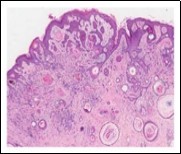

Lesions are generally superficial and infrequently invade lower dermis. Tendency for peri-neural or intra-neural infiltration, cogitated in adjunctive cutaneous carcinomas, is exceptional in desmoplastic trichoepithelioma. Nevertheless, desmoplastic trichoepithelioma can be exemplified as a component of particularly desmoplastic, cutaneous carcinomas demonstrating foci of peri-neural involvement 4, 5. Figure 1, Figure 2, Figure 3, Figure 4, Figure 5, Figure 6, Figure 7, Figure 8.

Figure 5.Desmoplastic trichoepithelioma enunciating several horn cysts, nests of basaloid cells, an enveloping desmoplastic stroma and thinned out superimposed epithelium 12.